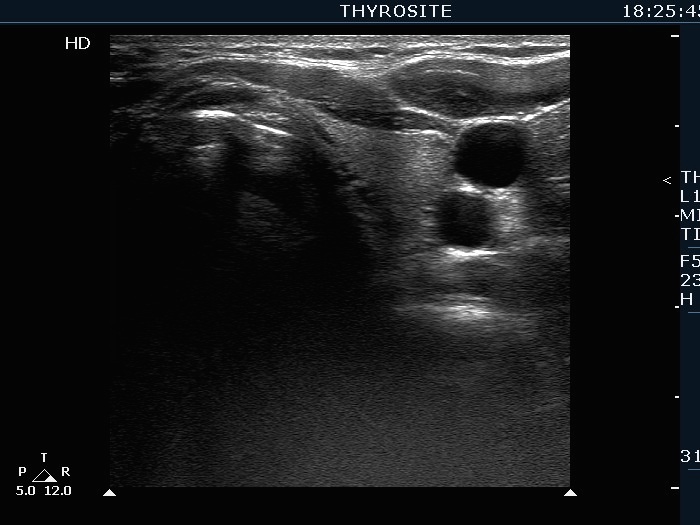

Extrathyroidal spread - case 2113 (ultrasonographic picture 10)

Left lobe, transverse scan. This lobe is intact.